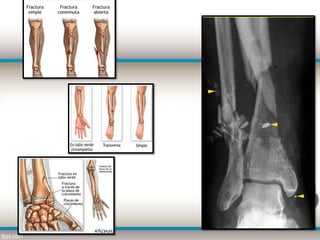

TIBIA

 La tibia es un hueso largo

de la extremidad inferior

que soporta el peso

del cuerpo .

 Se encuentra en la parte

anterior e interna de la

pierna, paralela y a un lado

del peroné. Se articula con

el fémur por arriba. Con el

astrágalo por abajo y con el

peroné por fuera y arriba.

FRACTURA CERRADA CON

MINUTA

FRACTURA

PERDIDA CONTINUIDAD

DEL HUESO

ABIERTA O

CERRADA        EXPUESTA